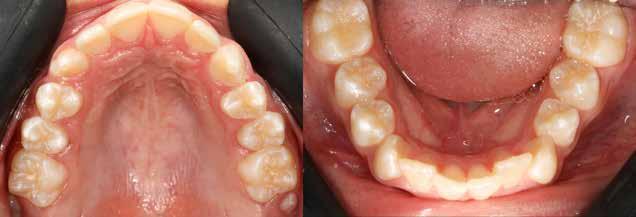

Dr. Ivana Dubovská, dr. Barbora Vágnerová, dr. Wanda Urbanová (Csehország), Dr. Veiszenbacher Éva, dr. Borbély Zoltán, dr. Borbély Péter (Dr. Borbély Fogszabályozási Stúdió, Budapest)

SZEMFOG ÉS KISŐRLŐ FORMÁZÁSA KISMETSZŐ APLÁZIA RÉSZÁRÁSSAL

TÖRTÉNŐ KEZELÉSE SORÁN

Absztrakt

A hiányzó oldalsó kismetszők részárással történő kezelése során a szemfogak és oldalsó fogak meziális mozgatása közben a fogszabályozó orvosnak csiszolással kell a fogak formáját igazítani. Már a kezelés elejétől a szemfog elcsiszolása nem csak az incizális részre kell hogy kiterjedjen, hanem az approximális, palatinális és a vesztibuláris felszín éli negyedére is. Így érhetünk el egy rövidebb klinikai koronát, a vesztibulo-orális méret csökkenését, egy incizális élet, valamint a szemfog megfelelő pozicionálását a kismetsző helyén. A túl széles szemfog megakadályozza a megfelelő interkuszpidáció kialakítását az oldalzónában. A palatinális felszín elcsiszolásával biztosítjuk az interferenciák nélküli metszővezetést, és a megfelelő overjetet a frontfogak enyhe érintkezésével. Ha a szemfogra a későbbiekben esztétikai pótlás készül, a megfelelő approximális elcsiszolás (az esztétikai fogorvossal történő egyeztetés után) biztosítja a zenith kívánatos pozícióját a későbbi felépítéshez. A mezializált kisőrlő palatinális csücskének elcsiszolására csak akkor van szükség, ha ez akadályozza a megfelelő fogérintkezést. Az első kisőrlő mindkét csücske fontos a már a szemfog helyén álló fog esztétikai és funkcionális beállításához.

A szemfog oldalsó kismetsző helyére történő bemozgatása során a fog átalakítása javasolt a két fog eltérő morfológiai adottságai miatt (1. a-b. ábra). A fog kontúrozása, vagy úgynevezett formázása magába foglalja az approximális felszínek elcsiszolását, valamint a többi fogfelszín igazítását a kívánt fogformának megfelelően [1].

Szemfog mezializációt követően történik az approximális felszínek igazítása. Elérjük a megfelelő mezio-disztális szélességet, és a kontaktpont incizális irányba helyeződik át. Ebben a fázisban mindig szükséges egyeztetni az esztétikai pótlást készítő fogorvossal a szükséges szemfogformáról és a későbbi felépítmény pontos helyzetéről. Az esztétikai fogorvosnak kell eldöntenie a meziális és disztális felszínek elcsiszolásának mértékét is.

A javasolt eszközhasználati sorrend a következő: piros gyémántfúró (finom 27-76 µm), sárga gyémántcsiszoló (extra finom, 10-36 µm) gyorsítóban megfelelő hűtéssel (5,6 ábra.). Alkalmazhatunk gyémántkorongokat vagy oszcilláló mozgásokat végző korongokat is. A polírozást Sof-Lex korongokkal vitelezzük ki (finom-narancssárga 3-40 µm, extra finom – narancssárga-sárga, 1-7 µm), [43,33], (7. a-b ábra). Az approximális felszínek elcsiszolása több lépésben történik megfelelő vízhűtés alkalmazásával és helyi fluoridálással.

3. a–b ábra: .019x.025” acél mint befejező fogszabályozóív vesztibuláris hajlításokkal a 11-13., a 21-23., valamint a 24-25. és a 14-15. fogak között. 4. a-b. ábra: A szemfog palatinális felületének formázása (a, Rodentica 257) és polírozása narancssárga Sof-Lex koronggal (b). A braketeket már eltávolították ezekről a fogakról.

Kisőrlő becsiszolása

Ha a szemfog helyére mezializált kisőrlő intrúziójára nincs is szükség, a palatinális csücsök akkor is akadályozhatja a harapást és a szemfogvezetést [44]. Ezekben az esetekben elcsiszoljuk a palatinális csücsköt (8. a-b ábra) piros gyémántcsiszolóval (finom, 27-76 µm, éli formázóval – Rodentica speciális tűhegy 806314466514031, Komet 8833 vagy GD – lándzsa Rodentica 806314257514020, Komet 0640) gyorsítóban (max 160 000 fordulat/perc) vízhűtés mellett, min. 50 ml/perc [39]. Extra finom sárga gyémántcsiszolóval polírozunk, 10-36 µm szemcsézettséggel (sárga éli csiszoló Rodentica speciális tűhegyű 806314466504031, GD – sárga lándzsa alakú Rodentica 806314257504020) és narancs Sof-Lex korongokkal (3M finom, narancssárga-alumínium-oxid kristály 3-40 µm nagysággal, extra finom, narancssárga-sárga, 1-7 µm alumínium-oxid kristályokkal) könyökdarabban (25 000 fordulat/perc) legalább 50 ml/ min. hűtéssel. Az elcsiszolást több lépésben végezzük, és ezt helyi fluoridalkalmazás követheti.

8. a-b. ábra: A páciens a felső első kisőrlő palatinális csücskének elcsiszolása előtt (a) és (b) után, a szemfogvezetés kialakításához. A szemfog vesztibuláris felszínének befejezése.